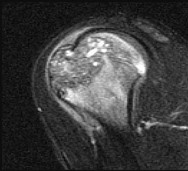

A 24-year-old rugby player has recurrent anterior shoulder instability with 25% anterior glenoid bone loss on a 3D CT scan.

A Latarjet procedure is performed. What is the primary biomechanical stabilizing mechanism of this procedure when the shoulder is in the apprehension position (abduction/external rotation)?

Explanation

The Latarjet procedure involves transferring the coracoid process with the attached conjoined tendon to the anterior glenoid. While the bony block restores the glenoid arc (the 'bony effect'), biomechanical studies have demonstrated that the primary stabilizing mechanism in abduction and external rotation is the dynamic 'sling effect.' The conjoined tendon acts as a hammock against the inferior capsule and lower subscapularis, preventing anterior translation of the humeral head.